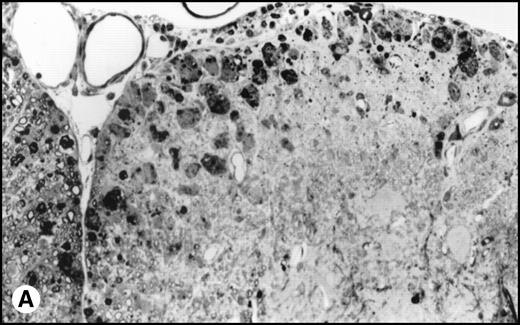

(A) Histology of SJL/J spinal cords from mice infected with TMEV. Section of spinal cord of an SJL/J mouse, 130 days after infection with TMEV. The right anterior column is completely demyelinated and numerous large lipid-laden macrophages are present close to the central sulcus. The gray uniform background reflects conspicuous gliosis in the demyelinated area (1-μm–thick, Epon-embedded section, stained with toluidine blue; original magnification × 220). (B) Section from spinal cord of an SJL/J mouse 130 days after infection with TMEV and after treatment with radiation and BMT. Inflammatory cells are still around the large venule in the parenchyma of the left anterior column, indicating active disease, but many axons are still surrounded by myelin sheaths and gliosis is less prominent (1-μm–thick, Epon-embedded section, stained with toluidine blue; original magnification × 220).

Interestingly, transplanted animals exhibited significantly higher titers of infectious TMEV within the spinal cord than did untreated controls (Fig 4). In transplanted mice, approximately 4-fold more infectious virus was present in the spinal cords than in the nontransplanted mice (12.6 × 103PFU/mg v 3.1 × 103 PFU/mg, P = .004). No viral plaques were found in the brain or spleen of either TMEV-infected group or in any tissues in the uninfected controls. Histologic examination of the spinal cords showed an acute inflammatory infiltrate with less glial scarring in transplanted mice versus a prominent chronic demyelination and gliosis with minimal residual infiltration in nontransplanted mice (Fig5).

Surviving mice displayed significantly diminished immune DTH responses to both virus and myelin epitopes, indicating the effectiveness of the myeloablative therapy (Fig 2). The acute neurologic deterioration correlated with an increased CNS viral load (Fig 4). Histologic evaluation (Fig 5) showed a predominance of acute gray matter inflammation in transplanted mice compared with predominant white matter demyelination in untreated animals. The slightly exacerbated clinical disease course, increased CNS virus levels, and pattern of histology are consistent with an exacerbation of direct viral cytopathology, not immune-mediated CNS damage. This finding is similar to that previously reported by Lipton and Dal Canto,11 who showed that high-dose cyclophosphamide or antithymocyte serum administered shortly after virus infection prevented TMEV-induced immune-mediated demyelination, but resulted in a mortality rate of 77% to 88%. Thus, severe immunosuppression of TMEV-infected animals is capable of causing fatal neurologic consequences that were also likely due to uncontrolled virus growth.